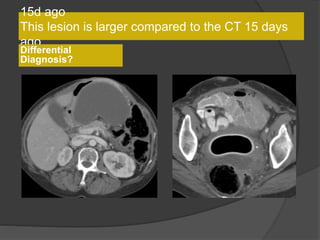

15d ago

This lesion is larger compared to the CT 15 days

ago

Differential

Diagnosis?

• Multilobulated thick-walled cystic lesion in the lesser sac and extending along the

adjacent peritoneal spaces and gastrohepatic ligament. Cystic lesion in the left

hemipelvis

• Minimal ascites, omental and mesenteric thickening

Present exam 15 days ago

Increased size

15 days

Present exam

Case 1 Diagnosis: Recurrent metastatic disease

with mucinous ovarian tumor